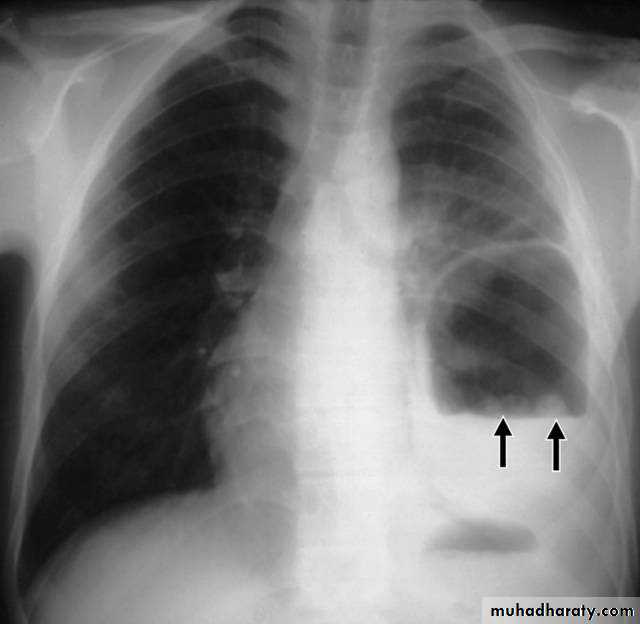

X-ray tension pneumothorax

X-ray pneumothorax